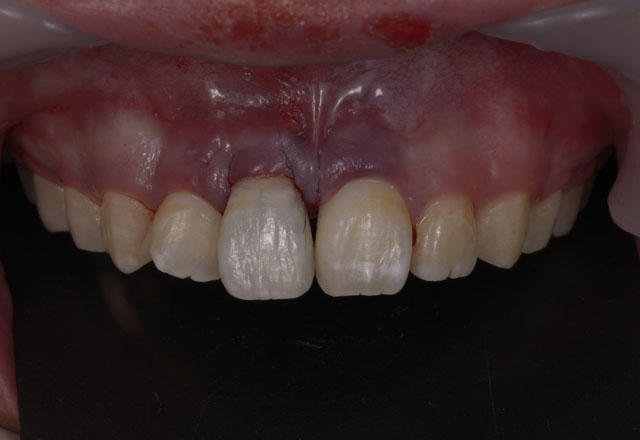

治療前のシミュレーション

施術前のレントゲン

― 治療後 ―

計画した位置に正確に施術することで良好な審美結果が得られます

コンピューターガイデッドインプラント治療 + 歯科用顕微鏡を用いたマイクロサージェリー 審美的に良好な結果が得られています

当院では、コンピューターガイデッド インプラント治療で正確な位置にインプラント手術を行い、そして前歯などの審美領域では顕微鏡を使用したマイクロサージェリー(顕微鏡下手術)を行うことで傷跡の目立ちにくい自然な仕上がりのインプラント治療を行っています。